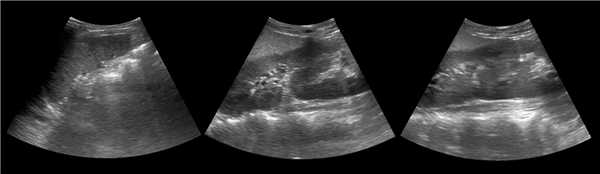

Рисунок. На УЗИ (1) и КТ (2, 3) контур почек волнистый. У эмбриона почка развивается из отдельных долек, которые сливаются по мере их роста. Дольчатое строение почек хорошо видно у плода и новорожденных, в единичных случаях сохраняется у взрослых.

Рисунок. Можно встретить горбатую левую почку — выпуклый неровный наружный контур из-за гипертрофии паренхимы в средней трети почки. Считают, что «горб» формируется у плода под давлением нижнего края селезенки.

Рисунок. Сканирование со стороны передней брюшной стенки позволяет не пропустить перешеек между почками. Перешеек спереди от позвоночника является доказательством сращения почек — подковообразная почка. Варианты анатомии подковообразных почек смотри здесь.